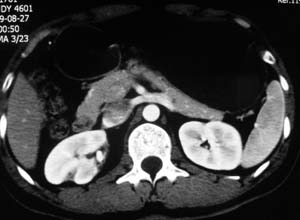

以下是引用子期在2010-3-19 20:47:00的发言:[br]血管畸形的ct增强应该有明显强化,本例并不相符合。本例双肾局部的略低密度影,累及肾盂,局部皮质明显变薄、内陷,增强扫描有轻度的强化,应考虑为炎性病变,患者为年轻男性,累及双肾的感染以结核较常见,可以没有明显的临床症状,尿中有时候也并不能查出什么;肾脓肿常有明显感染中毒症状,本例不符,另外一般的肾盂肾炎或肾小球肾炎通过小便就可确诊,其它还不能排除的是黄色肉芽肿性肾盂肾炎,然而单凭ct一般也很难鉴别。